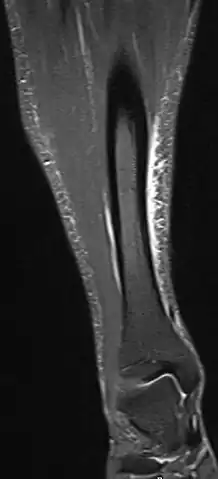

Shin splints

Other names: Medial tibial stress syndrome (MTSS),[1] soleus syndrome,[2] tibial stress syndrome,[2] periostitis[2]

A shin splint is pain along the inside edge of the shinbone (tibia) due to inflammation of tissue in the area.[1] Generally this is between the middle of the lower leg to the ankle.[2] The pain may be dull or sharp and is generally brought on by exercise.[1] It generally resolves during periods of rest.[3] Complications may include stress fractures.[2]

Shin splint pain is described as a recurring dull ache, sometimes becoming an intense pain, along the inner part of the lower two-thirds of the tibia.[4] The pain increases during exercise, and some individuals experience swelling in the pain area.[5] In contrast, stress fracture pain is localized to the fracture site.[6]

Other potential causes include stress fractures, compartment syndrome, nerve entrapment, and popliteal artery entrapment syndrome.[16] If the cause is unclear, medical imaging such as a bone scan or magnetic resonance imaging (MRI) may be performed.[3] Bone scans and MRI can differentiate between stress fractures and shin splints.[11]